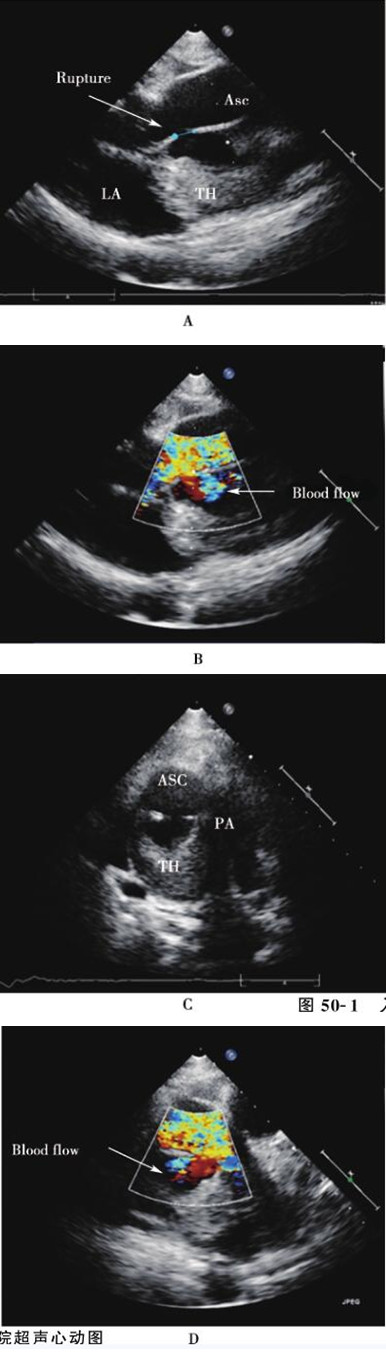

入院后进一步完善超声心动图:左心房上方探及一等回声团块,大小3.6cm×3.5cm,回声欠均匀、边界不清晰,部分与左心房壁、主动脉后壁粘连;升主动脉后壁距主动脉瓣约1.2cm处探及回声失落,大小约0.7cm,后方为无回声区,该无回声区位于占位右前方,彩色多普勒于回声失落处探及升主动脉与无回声区收缩期双向血流交通信号,最大流速约0.9m/s;占位左侧为肺动脉主干、右肺动脉,主肺动脉、右肺动脉右侧边界显示不清晰,彩色多普勒示肺动脉内血流未见明显异常。结论:左心房上方占位,性质待查 (肿瘤?血栓?),占位与主动脉后壁粘连,假性动脉瘤形成可能性大,不除外占位累及肺动脉主干、右肺动脉可能(图50-1、50-2)。

图50-1 入院超声心动图 A:主动脉长轴切面示距离主动脉根部约2cm处可见一约1cm的破口,主动脉后壁后方可见一无回声区(2.5cm×1.7cm),为假性动脉瘤;无回声区后方可见一等回声团块,大小3.5cm×3.6cm,为假性动脉瘤内血栓形成,并压迫右肺动脉;B:主动脉长轴切面彩色多普勒示收缩期血流从主动脉经破口至主动脉后壁后方无回声区;C:升主动脉短轴切面示主动脉后壁破口和血栓;D:升主动脉短轴切面彩色多普勒示收缩期血流从主动脉经破口至主动脉后壁后方无回声区。Ruptue:破口;LA:左心房;Asc:升主动脉;TH:血栓;PA:肺动脉